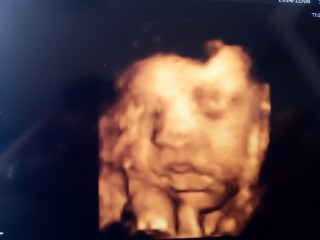

写真:32w1d:ケイトさん:こんなに開いたパー

なかなかお顔を見せてくれない息子ちゃん、今日のエコーでは手のひらを大きく開いてパーをして顔を隠していました(笑)先生もこんなに開いたパーをは珍しいね、と言ってくれました(^^)